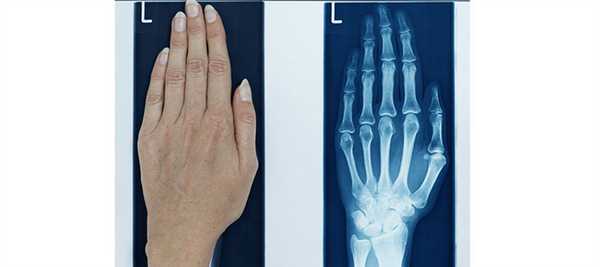

Снимок кисти руки - это самое первое исследование внутренней структуры тела человека, которое было сделано путем проецирования степени ослабления Х-лучей в виде изображения на пленку. На тот момент Вильям Рентген еще не знал, что даже спустя два века такой способ диагностики будет самым информативным в случае травм и патологических изменений в суставах и костях. Кроме того, было обнаружено, что рентген кисти дает возможность достаточно точно определить анатомический возраст любого человека, а также его резервы роста.

- Прямая проекция. Для такой съёмки кисть укладывается горизонтально, на стол - тыльной стороной или ладонью. Лучи рентгена будут проходить через кисть перпендикулярно кассете с плёнкой. На таком снимке будут определяться все кости запястья, за исключением гороховидной. Также будут видны лучезапястный сустав, пястные кости, запястно-пястные суставы, межзапястный сустав и фаланги пальцев.

Расшифровку рентгена кистей рук делает специалист-рентгенолог сразу после завершения съёмки. Он оценивает взаимное расположение костей кисти, их соединение между собой, целостность. Также уделяется внимание оценке структуры и плотности костей.

Нормальные показатели

В норме кости кистей рук должны иметь однородную структуру. На снимках не должно быть затемнений на белых участках. Между костями должна присутствовать щель.